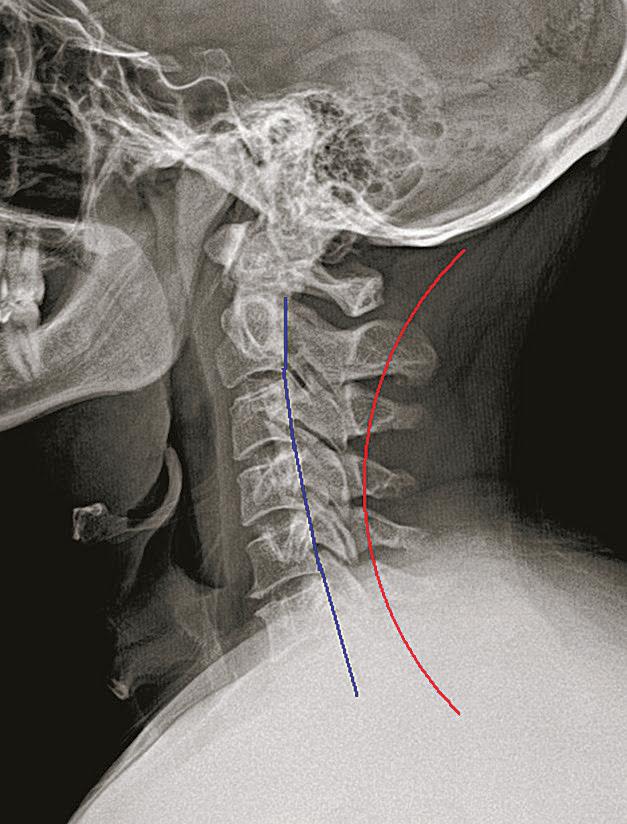

16 Concord Insider T h u r s d a y , M a rc h 7 , 2024 complete exam $59 Chiropractic… because the body heals itself. with x-rays, if necessary For over 23 years people have come to us for help with: Sciatica Neck Pain Low Back Pain Digestive Problems Enhanced Performance Headaches and Migraines Chronic Ear Infection Numbness/ Tingling in Hands *results may vary Route 104 & 3 3 Annalee Place (603)677-1444 MEREDITHPEMBROKEEPPING Route 106 & 3 556 Pembroke St. (603)224-4281 Route 125 & 155 629 Calef Highway (603)679-3222 Colic ADD/ADHD Overall Wellness Village Shoppes Route 101 (603)575-9080 BEDFORD Health is Our Greatest Wealth Is poor spinal alignment affecting yours? Congratulations Brian F. March Crossroads Chiropractic Practice Member of the Month BEFORE AFTER The nervous system controls and coordinates all functions of the body, making its proper functioning essential for overall health. Structural shifts in the spine can obstruct the nerves and interfere with their function. Chiropractors refer to these obstructions as vertebral subluxations, and they are at the core of chiropractic care. Find out if subluxations are affecting your health with a chiropractic examination with any necessary x-rays for just $59 this month at any Crossroads Chiropractic location. Massage Therapy now offered in Pembroke location! Deep tissue and sports massage only $79/ hour. Book online at CrossroadsChiropractic.com Asthma